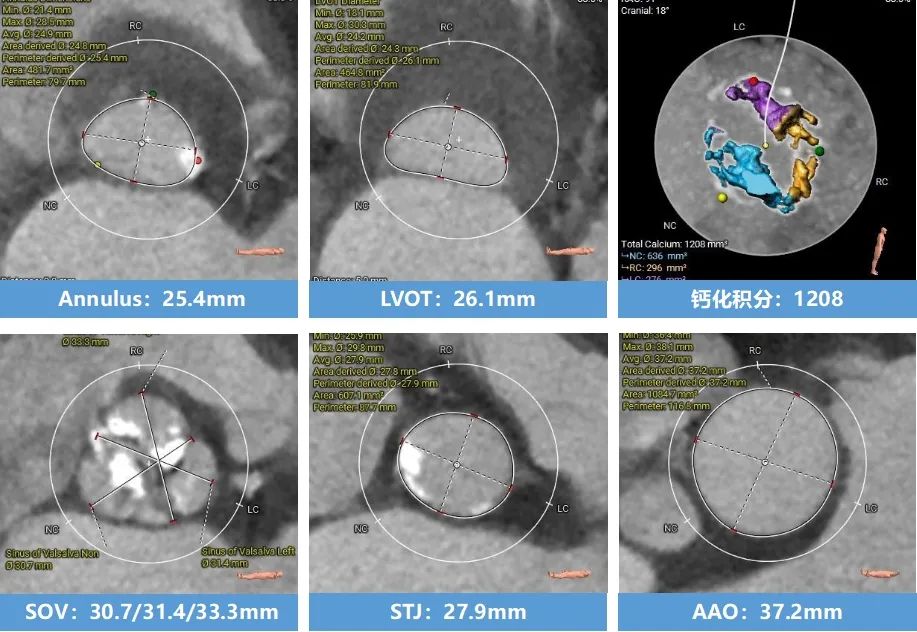

术前CT分析(76岁,女性)

▶ Type1型二叶式主动脉瓣(L-R),瓣叶增厚,重度钙化,钙化分布不均匀,无窦钙化延申至STJ以上,LVOT偏直筒型。

▶ 左右冠脉开口高度尚可,左窦瓣叶切线测量距离>冠脉开口下缘到根部距离。

▶ 心室腔内径尚可,心室壁厚度可,心尖尚可。

▶ 瓣环水平夹角72°,横位心,主动脉弓角、弓距尚可。

主动脉根部测量

瓣上结构测量